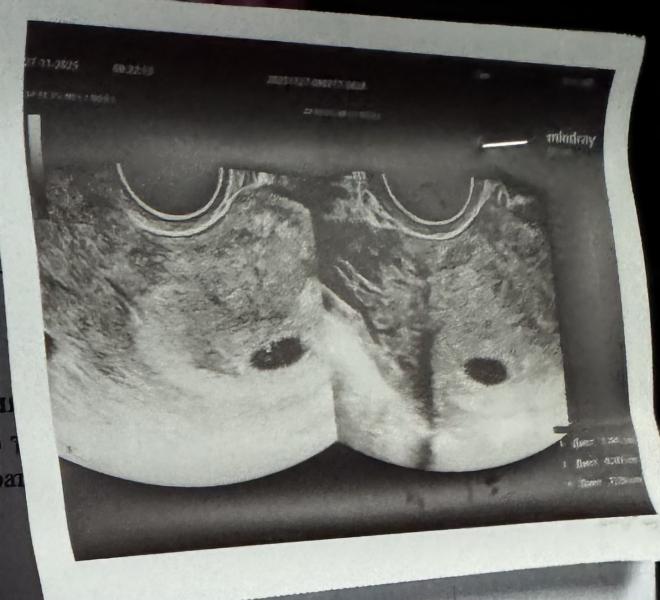

Первый цикл после родов и сразу победный🌸 вторую беременность ждали почти год, так что особо сильно не надеялись на этот цикл, он получился очень длинный, по узи 5-6 недель, по кд 8 недель🤣